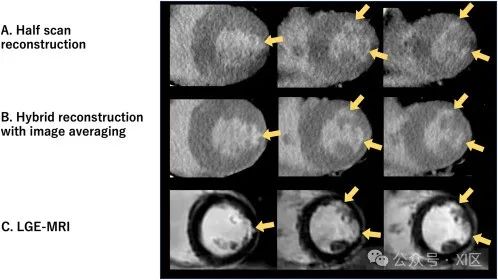

CT-LE的定义是在注射造影剂后进行延迟成像,以评估心肌的延迟强化情况。由于 CT-LE中正常心肌与延迟强化心肌之间的对比度远低于LGE-MRI,因此应优化成像参数以增强心肌对比度。很多方法的实用性已经得到证实,比如迭代重建、深度学习重建和图像平均等,可抵消由于使用低管电压而增加的图像噪声。与CCTA通常使用的高对比度目标图像重建相比,建议使用低对比度目标图像重建。图像噪声水平取决于辐射剂量;因此,过低的辐射剂量可能会降低图像质量和ECV定量。虽然半扫描重建(扫描仪从围绕患者旋转的180° 而非360° 范围内获取数据来创建图像的技术)因其提高了CCTA的时间分辨率而受到青睐,但全扫描重建可能更适合心率稳定的患者,因为它能利用足够的辐射剂量来提高图像质量。在双源CT中,与半扫描重建相比,融合了半扫描和全扫描技术的混合重建算法可提高图像质量和观察者间的再现性。

在一名无心肌梗死病史的患者中,通过传统半扫描和混合重建进行CT-LE成像的比较。侧壁和前壁的心内膜下梗死(箭头)由于条纹状伪影(A)而难以用半扫描重建法识别。然而,使用图像平均的混合重建(B)可以清晰地观察到它们,并显示出与LGE- MRI的极佳相关性(C)。多能量CT是一项相对较新的技术,可获取不同能量的衰减数据。它提供的图像集包括碘特定图像、虚拟平扫图像、有效原子序数图像和虚拟单色图像(VMI)。在40-50 keV下获取的VMI有助于更好地直观评估CT-LE的延迟强化,因此应进行重建。碘特异性图像可提高对比度与噪声比,并在无平扫数据的情况下提供ECV。